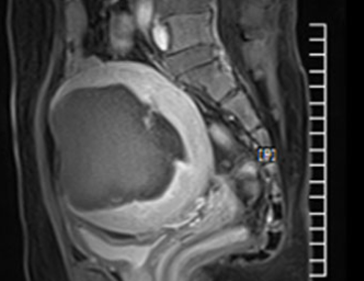

• 시술 전

시술 후